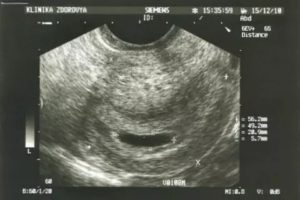

Гинекологи отдают предпочтение трансвагинальному УЗИ, которое дает четкую картину состояния органов малого таза. Оно может назначаться беременным женщинам, так как помогает проследить за развитием плода, выявить даже незначительные аномалии и определить причину повышенного тонуса живота. Почему предпочтительна именно такая диагностика в каждом случае решает врач.

Преимущество вагинального УЗИ заключается в том, что оно позволяет разглядеть даже мелкие кисты яичника, воспалительные процессы, миомы.

У беременных женщин анализы (мазок) и такое обследование способно дать точную оценку развитию плода. Если присутствует гипертонус, диагностика определяет причину его повышения и помогает принять меры по устранению угрозы.

Данная процедура – единственный вариант информативного осмотра пациенток с ожирением.

Следует помнить, что при всех своих преимуществах, трансвагинальное УЗИ имеет ряд недостатков. Сама процедура многими женщинами отмечается как неприятная, а после нее иногда появляются коричневые выделения, живот удерживается в напряжении (тонус) и может начать болеть низ спины. В норме все эти симптомы слабо выражены и вскоре проходят.Перед УЗИ рекомендуется сдавать мазок на инфекции. Мазок чаще всего берут из уретры, шейки матки и влагалища. Это помогает определить наличие воспалений или ЗППП.

В сочетании с результатами ультразвукового исследования, мазок помогает быстро выявить причину воспалений, увеличения яичника и болей внизу живота.

После УЗИ малого таза выделения возникают редко. И порой вообще не имеют никакого отношения к проведенному исследованию. Если они белые или молочного цвета, то это не является признаком какой-либо патологии. Их обильное выделение обусловливается механическим воздействием на цервикальный канал, во время которого присутствует раздражение желез и повышенная ими выработка слизи.

А вот если у женщины отмечается появление кровянистых или мажущих темных выделений после УЗИ, то в этом случае следует насторожиться, так как такое явление может сигнализировать о различных патологиях, связанных с отслоением или предлежанием плаценты.

При этом у будущей мамочки может отмечаться слабость, тянущая боль в животе и другие симптомы, указывающих на необходимость специального лечения.

Отслоение и предлежание плаценты не является следствием проведенного УЗИ, даже если их проявления ранее не отмечались.Возникновение симптомов этих патологий обусловливается механическим воздействием на органы малого таза, в результате чего скопившаяся кровь начинает выходить из них естественным путем.